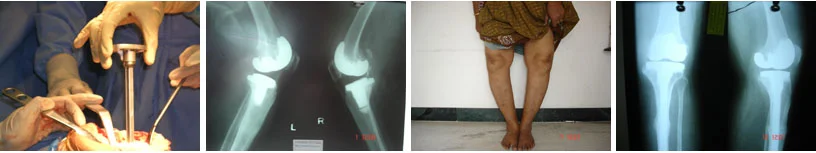

Primary total knee replacement helps relieve severe knee pain and stiffness caused by arthritis or long-term joint damage. The procedure restores smooth movement and allows patients to resume daily activities with improved comfort.

From diagnosis to surgery and recovery, our team ensures you receive expert treatment and individual attention throughout your treatment journey